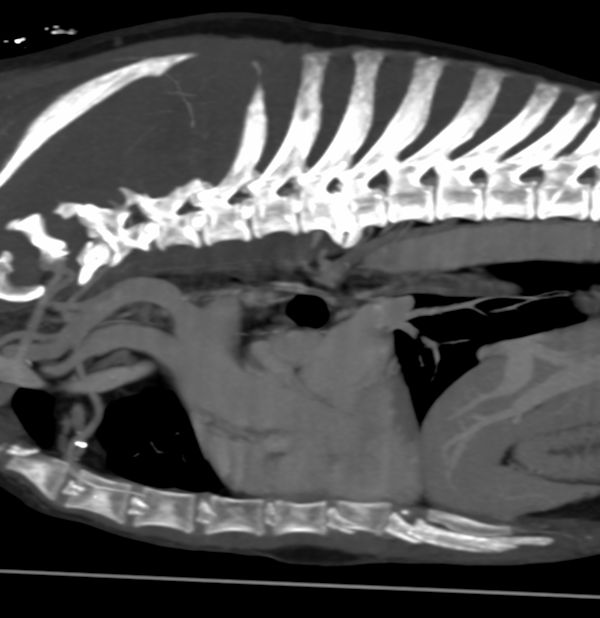

Radiology Support

Need a hand with radiographs, CT, MRI or US loops? We’ve got you covered. Our team provides detailed, high-quality reports to support you in managing your cases.

In addition to interpreting images, we can also provide imaging protocols for specialized CT or MRI studies (for example: urinary tract excretory contrast CT, lymphangiography, etc.). Let us know if you have questions about the imaging in advance.

Over the years, we’ve learned that imaging reaches its full potential when interpreted in context. That’s why for radiographs, CT, MRI, and ultrasound cases, our radiologist can collaborate with clinical specialists who can review the case in depth. After reviewing the images, the specialist can discuss the next steps with you—from further work-up to treatment planning.